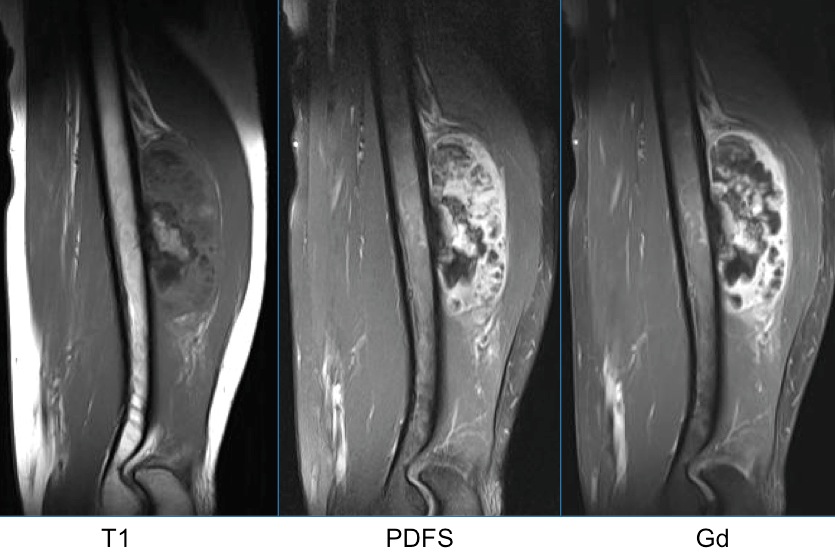

Figure 2 for case Parosteal osteosarcoma ( RID4021 )

Figure 2